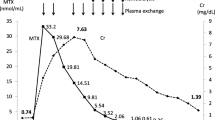

Figure 1a shows the drop in serum MTX level with different treatment options. The sequential use of CHP and SPAD was shown to lower MTX faster than leucovorin alone (Fig. 1b). The MTX clearance was up to 70 mL/kg/h at the commencement of therapy (Fig. 1c). Urine MTX clearance increased dramatically 140 h later as renal function and urine output improved. Serum creatinine normalized on day 14 of treatment. Her serum creatinine was 48 μmol/L with eGFR of 112 mL/min/1.73 m2 upon discharge from the intensive care unit. No major complications, such as severe marrow failure or mucositis, were detected, despite exposure to such toxic levels of MTX. After this episode, HDMTX was replaced by ifosfamide and etoposide in the chemotherapy protocol.

a This diaphragm showed the drop in methotrexate (MTX) over time. The timing of different treatment methods was shown. The blue arrow line represents the timing and duration of leucovorin treatment. The green arrow line represents the timing of single-pass albumin dialysis (SPAD) and the purple arrow line represents the timing of the two sessions of charcoal hemoperfusion (CHP). The red circles showed the drop in serum MTX after each session of CHP, i.e., the curve in the red circles showed a steeper slope, indicating a more rapid drop in serum MTX. b We use the trend line method and assume a first-order kinetic for MTX elimination to predict the drop in the MTX level with different methods of treatment. The broken line with purple dots represents the predicted clearance of MTX by leucovorin alone. The broken line with orange dots represents the predicted clearance of MTX by leucovorin and SPAD. The broken line with yellow dots represents the predicted clearance of MTX by leucovorin with SPAD and CHP. The combination of all three modalities of treatment achieves the highest elimination rate of MTX. c The graph shows the changes in serum creatinine with MTX clearance by SPAD and urine. Dialysis MTX clearance is best when serum MTX is highest and during the period of impaired renal function. Urine MTX clearance improved as renal function recovered from MTX toxicity and urine output increased